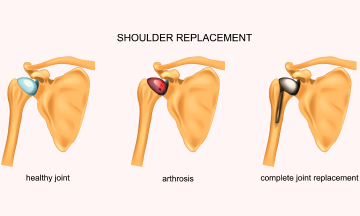

Arthritis also called wear and tear of the shoulder joint, can be due to several causes such as old age, untreated muscle tendon tears, instability, old sepsis or inflammation in the joint. A completely arthritic joint is most painful condition and will require a joint replacement surgery.

Shoulder arthroplasty, also known as

Shoulder replacement surgery, also known